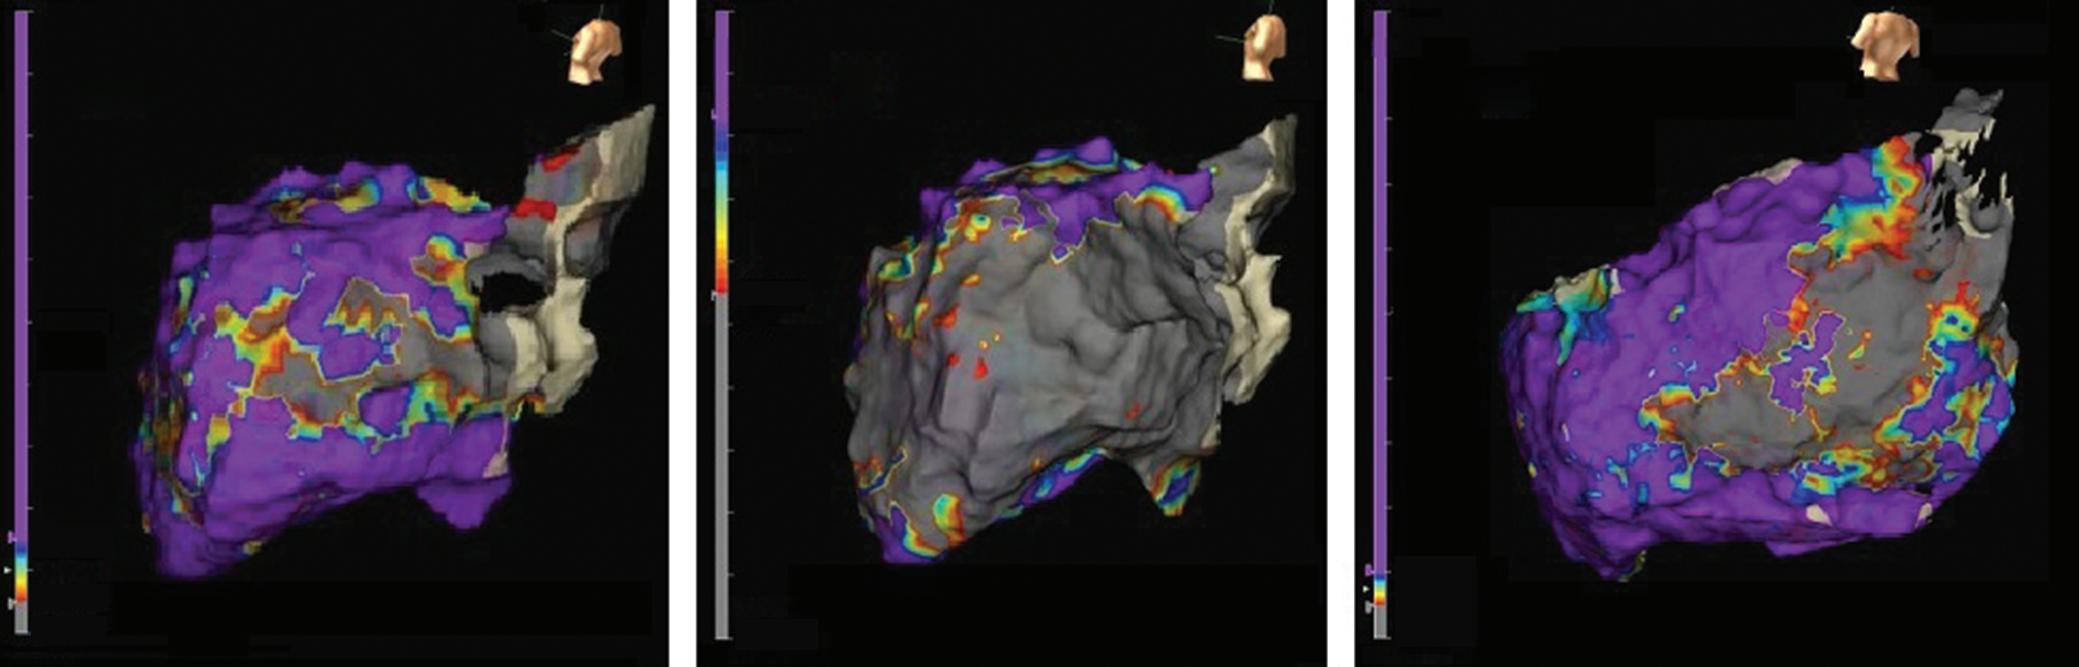

Figure 7: Assessing Elimination of Arrhythmogenic Fibrotic Substrate by Late Gadolinium Enhancement-MRI

Against this background, we have recently analysed the potential role of LGE-MRI to assess the long-term effect of VT ablation in terms of arrhythmogenic substrate elimination (unpublished data). Three to 6 months following the procedure, effective ablation was reflected by pronounced reduction of LGE-MRI-detected border zone scar volume and extent of slow conduction channels compared to the preprocedural LGEMRI (Figure 7). In patients undergoing repeat ablation procedures, this arrhythmogenic substrate elimination as determined by LGE-MRI correlated well with EAM. Thus, LGE-MRI-based lesion assessment may be of potential value to evaluate the efficacy of ventricular substrate ablation and to predict VT recurrences and clinical outcome. However, as mentioned above, clinical validation is warranted.

Left panel: LGE map of the left ventricle prior to substrate-based ventricular tachycardia ablation. LGE depicts an antero-apical scar. A 3D-analysis using the ADAS 3D software predicts a slow-conduction channel (black line) extending over 30 % of the transmurality that was confirmed by invasive electroanatomical mapping. Right panel: LGE map of the left ventricle 3 months post-ventricular tachycardia ablation. LGE indicates complete scar homogenisation and ‘dechannelling’ with ablation lesions covering the full substrate. Percentages indicate distinct layers of the transmurality from endocardial (0%) to epicardial (100%). LGE = late gadolinium enhancement.